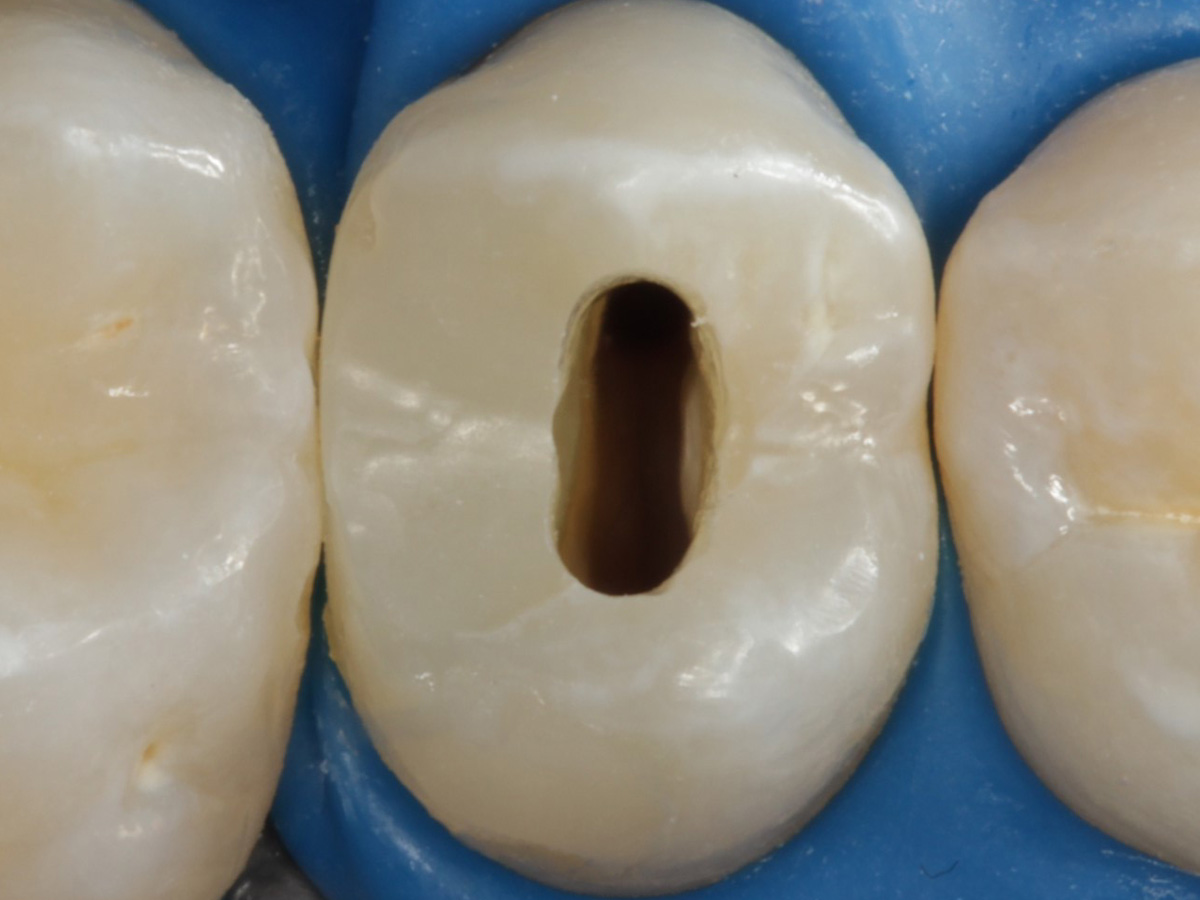

Abbildung 24

Folgesitzung: Trepanation Zahn 25

Abbildung 25

Nadelaufnahme nach elektronischer Längenmessung